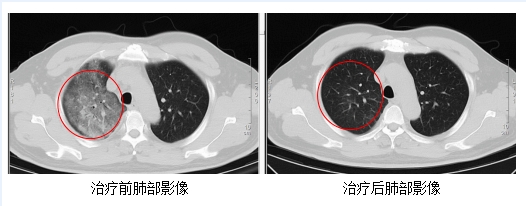

發(fā)熱門診醫(yī)生詳細詢問顧先生的既往病史,并為其進行細致的體格檢查。胸部CT結(jié)果顯示,顧先生的雙肺存在大面積的炎癥病變。

在感染科醫(yī)護團隊的精心治療與細致護理下,顧先生的發(fā)熱、咳嗽、胸悶等癥狀逐漸緩解。復(fù)查的CT結(jié)果顯示,肺部炎癥情況得到了明顯的改善。目前,顧先生已經(jīng)順利康復(fù)出院。